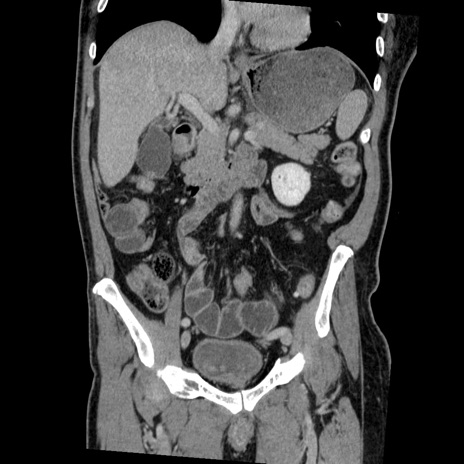

症例22(冠状断像)

【症例】50歳代男性

【主訴】腹痛

【現病歴】AVMからの被殻出血のため回復期リハ病棟入院中。 本日午後3時頃急に下腹部痛が出現した。

【既往歴】AVM、被殻出血、虫垂炎、高血圧

【身体所見】意識晴明、左半身不全麻痺、会話の理解は良好、36.5°C、腹部:膨隆、全体に板状硬、下腹部正中に圧痛点あり、反跳痛-、筋性防御不明、右下腹部にope scar

【データ】WBC 9400、CRP 0.06